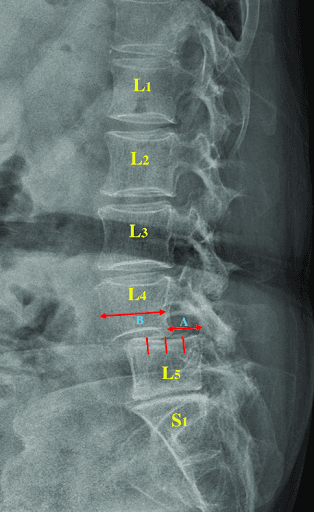

Spondylolisthesis occurs when one vertebra slips forward over the one below it.

It most commonly affects the L5–S1 and L4–L5 levels.

Degrees of Severity

Grade I

- 0–25% forward slip

- Mild severity

Grade II

- 26–50% forward slip

- Moderate severity

Grade III

- 51–75% forward slip

- Severe

Grade IV

- 76–100% forward slip

- Very severe

Most people with Grade I–II respond well to conservative, non-surgical care.